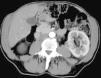

Objetivo. El oncocitoma es un tumor renal benigno, relativamente infrecuente. Hasta este momento su diferenciación radiológica del carcinoma de células renales se considera imposible, aunque hay escasos artículos en que se haya utilizado la tomografía computarizada (TC) trifásica. Los autores describen los hallazgos con TC trifásica en estos tumores, valorando si algunas características, aunque no diagnósticas, sí pudieran sugerir la posibilidad de este diagnóstico. Esto, en algunos casos, podría cambiar el manejo de los pacientes. Material y métodos. Se describen los hallazgos de TC trifásica en 10 casos de oncocitoma, vistos en 8 pacientes (un caso era multifocal-bilateral). En todos los casos el diagnóstico fue anatomopatológico, en la pieza de resección. Resultados. Todos los tumores fueron hallazgos ecográficos incidentales previos a la TC, presentando un tamaño muy variable, de 3 a 15 cm, con una media de 5,2 cm. El contorno era bien definido. Uno de los pacientes tenía tumores bilaterales (2 derechos y 1 izquierdo). Excepto en un tumor, el resto mostraban una cicatriz «estrellada» interna, que en un caso seguía un marcado patrón lobular. La captación tumoral de contraste fue ávida, con una media de 120 HU en fase arterial y 116 HU en fase excretora. La evolución de todos los pacientes fue buena, no detectándose recidivas postquirúrgicas. Conclusiones. Aunque la diferenciación con el carcinoma de células renales no puede hacerse con certeza, debe sugerirse la posibilidad de oncocitoma, fundamentalmente en tumores pequeños, con cicatriz central, ausencia de necrosis, falta de infiltración y un patrón de captación como el que se describe. Independientemente del tamaño, una morfología lobular del tumor también debe sugerir esta posibilidad.

Objective. Oncocytoma is a relatively uncommon benign kidney tumor. To date, it has been impossible to differentiate this tumor from renal cell carcinoma radiologically, although few articles report on the use of tri-phase CT in this tumor. We describe the triphasic CT findings in these tumors and evaluate whether some characteristics, although not sufficient to ensure the diagnosis, can suggest the possibility of oncocytoma. In some cases, this may lead to a different approach to the management of patients. Material and methods. We describe the tri-phase CT findings in 10 cases of oncocytoma in eight patients (one case was bilateral and multifocal). The diagnosis was made after histological examination of surgical specimens in all cases. Results. All the tumors were found incidentally at ultrasound examination prior to CT study. Tumors all had well-defined borders, and their size ranged from 3 to 15 cm, with a mean diameter of 5.2 cm. One patient had bilateral tumors (2 right and 1 left). All but one of the tumors had a star-shaped scar inside, with a marked lobular pattern in one case. All tumors showed avid uptake, with mean enhancement of 120 HU in the arterial phase and 116 HU in the venous phase. All patients evolved favorably with no post-surgical relapse. Conclusions. Although oncocytoma cannot be differentiated from renal cell carcinoma with certainty, the possibility of oncocytoma should be suggested in the case of small tumors with a central scar, without necrosis or infiltration, and an enhancement pattern as described here. Regardless of the size of the tumor, lobular morphology should also suggest this possibility.